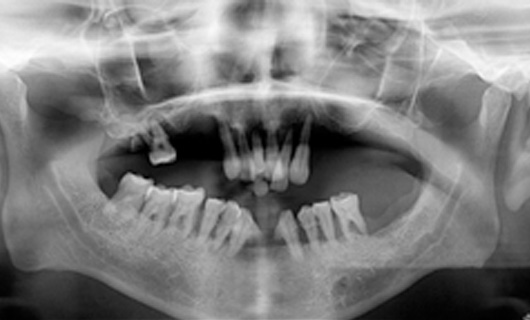

After placing dental implants, your dentist will fabricate dentures in the following steps:

- Impressions: After your gums are substantially healed and healthy, your dental assistant or dentist will make an impression of jaws.

- Modeling prosthesis: Your dentist will make a wax model of the dentures before fabricating the final product to check for fit and appearance. Modifications will be done at this stage to match the patient’s expectations regarding teeth size, shape, and color.

- Fabrication of final denture: Once you and your dentist have decided on a final fit and appearance, a dental technician or prosthodontist will construct a final prosthesis that is durable and natural-looking.

- Insertion: Once your final dentures are made, they are fixed to dental implants in the jaw bone.